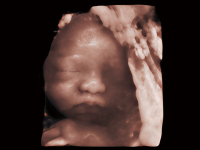

作為開(kāi)立醫(yī)療全新打造的超高端旗艦超聲產(chǎn)品,從探頭抬起喚醒開(kāi)啟掃查到多維探頭發(fā)射接收,通過(guò)先進(jìn)的場(chǎng)成像發(fā)射、自適應(yīng)聚合重建等技術(shù),基于RF Data原始射頻數(shù)據(jù)在圖像生成、高端功能等方面實(shí)現(xiàn)突破,為婦產(chǎn)科、兒科提供全方位臨床解決方案。

夢(mèng)溪?P80以“關(guān)愛(ài)女性”為基石,提供全方位的解決方案,量身定制以滿足女性的健康需求,涵蓋婦科、生殖健康檢查、產(chǎn)前篩查及產(chǎn)后康復(fù)等領(lǐng)域。